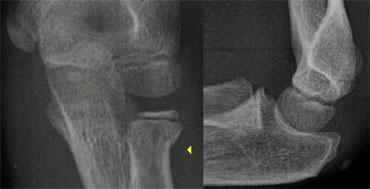

Chấn thương khớp khuỷu tay thường là kết quả của tình trạng duỗi quá mức hoặc vẹo ngoài quá mức do ngã chống tay ra phía trước.

Cuộn qua các hình ảnh ở bên trái để xem cách duỗi quá mức dẫn đến gãy xương trên lồi cầu.

Tình trạng tràn máu khớp sẽ dẫn đến sự dịch chuyển của đệm mỡ phía trước lên trên và đệm mỡ phía sau ra phía sau.